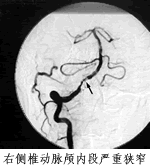

本报讯 (驻地记者 匡远深)北京天坛医院放射科主任医师姜卫剑等采用血管内支架技术,治疗椎基底动脉供血不足获得成功,半年间完成手术10例,无死亡、无并发症。

国外最早于5年前曾报道血管内支架治疗椎基底动脉狭窄。到目前为止,有文献记载的手术病人不足50例,其中还有一定的死亡率,国内一直未见报道。该治疗方法风险较大,要求操作医师的介入技术要精,看片(各种神经影像)水平要高,捕捉病变要准,还要具备丰富的神经内科疾病知识。只有这样,才能制定完善的治疗计划,把术中风险降至最低值。